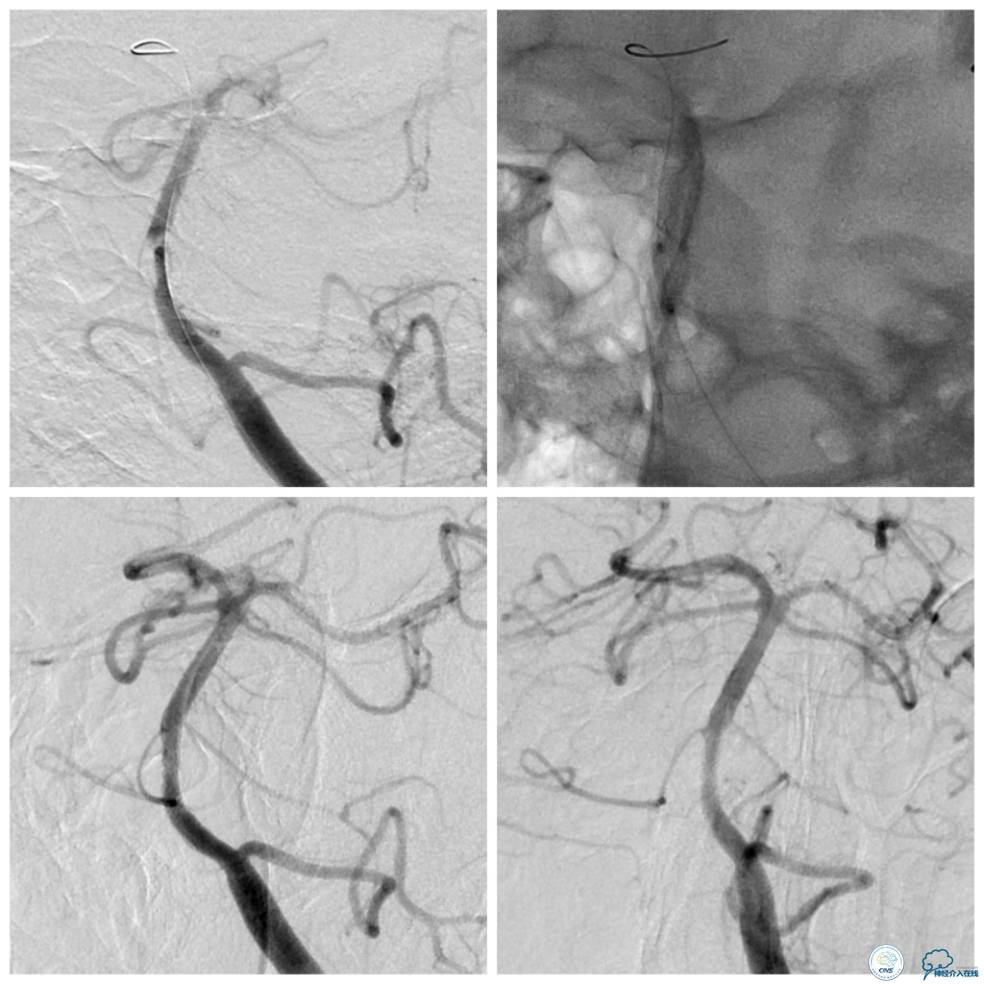

术前造影(图5、6):基底动脉近段狭窄,局部管腔不规则,似有“充盈缺损样改变”,管壁不光滑,前向血流减慢。可见右后交通动脉开放,见双侧大脑后动脉,基底动脉尖和上段显影。

遂换用Traxcess微导丝(0.014″200cm)+Echelon-10微导管越过狭窄段后,重新交换Transend微导丝至右大脑后动脉P2段,Gateway球囊(2.0mm×9mm)扩张后,放置Apollo支架(2.5 mm×13mm)至狭窄段,球扩释放后支架贴壁良好,残余狭窄约15%,前向血流TICI3级(图8)。